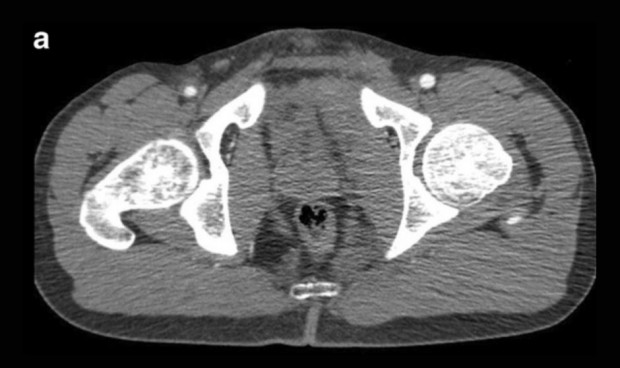

Imagen de pelvis.

Una investigación realizada en el Hospital Universitario de Oslo, y publicada en la revista Springer Open ha evidenciado que una exploración de tomografía computarizada en la fase arterial parece no mejorar el diagnóstico para identificar a pacientes con traumatismo pélvico que recibieron una intervención angiográfica a petición del cirujano traumatólogo.

Los expertos diagnosticaron las lesiones arteriales pélvicas en la angiografía por tomografía computarizada y añadieron una fase arterial a exploración de fase venosa portal más extendida. “Las lesiones arteriales se ven como extravasación en las imágenes arteriales o como hematomas en aumento en las imágenes tardías, mientras que las lesiones venosas carecerían de extravasación de contraste en la exploración arterial temprana”, señalan los investigadores

El objetivo fue determinar si existe un beneficio diagnóstico de una tomografía computarizada arterial adicional para predecir la decisión de derivación para una intervención angiográfica. “ Comparamos un conjunto de imágenes venosas de portal único con un conjunto combinado de fases venosas arteriales y portales”, explican los especialistas.

Los hallazgos positivos de la tomografía computarizada en la fase venosa de portal solo tuvieron una sensibilidad y especificidad del 62 por ciento y el 86 por ciento, frente al 56 por ciento y el 93 por ciento para los hallazgos simultáneos en la fase arterial y venosa portal.

La especificidad fue significativamente mayor para los hallazgos positivos en ambas fases en comparación con la fase venosa portal solamente. La aplicación de un umbral> 0,9 cm de diámetro de extravasación a la fase venosa portal sólo dio como resultado una sensibilidad y una especificidad idénticas a las de ambas fases.